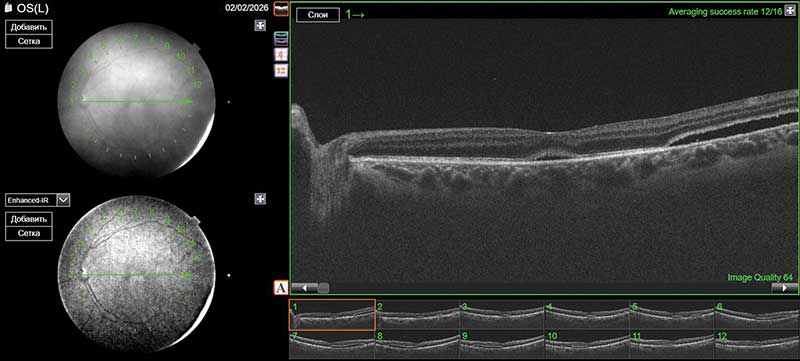

Рис. 2. ОКТ макулярной области левого глаза после первого этапа операции (тампонада силиконовым маслом; отмечается прилегание сетчатки с сохранением небольшой субретинальной полости)

На первые сутки после операции МКОЗ левого глаза составила 0,2. Сетчатка прилежит во всех отделах, зона ретиношизиса и разрыв блокированы лазеркоагулятами. Офтальмогипертензия (ВГД OS – 28 мм рт. ст.) купирована с помощью инстилляций гипотензивных капель. Пациент выписан на вторые сутки под амбулаторное наблюдение с соответствующими рекомендациями (рис. 1 и 2).